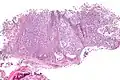

Low mag.

Low mag. High mag.